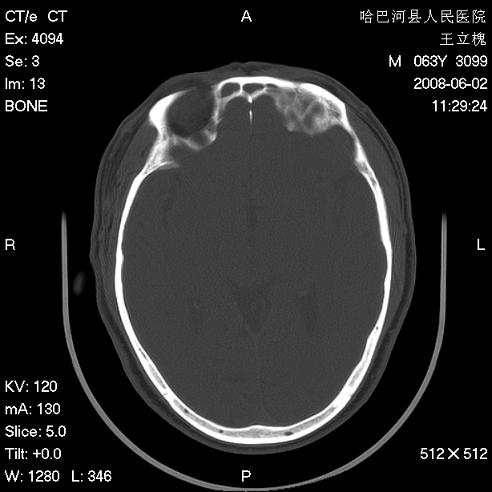

标题: CT13803:反复性鼻塞、流涕一年余 [打印本页]

标题: CT13803:反复性鼻塞、流涕一年余

1.全组副鼻窦炎2.双侧上颌窦积液

全组副鼻窦炎

.全组副鼻窦炎2.双侧上颌窦积液

1)全副鼻窦炎(左侧上颌窦黏膜下囊肿或息肉)。2)左眼眶肌锥内不规则小结节状软组织密度影;考虑为小血管瘤可能。建议行ct增强扫描检查。

全组副鼻窦炎,左侧肌锥内不规则形软组织肿块影,与眼外肌密度相当,左侧视神经受压,肿块与视神经及眼外肌分界清晰,眼外肌无增粗,眶壁无破坏,球后脂肪间隙不模糊,考虑良性改变,小血管瘤或神经源性肿瘤可能,建议增强扫描。